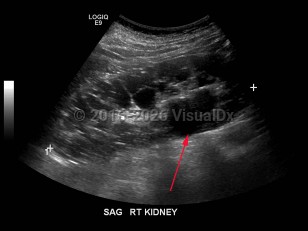

Pyelonephritis

Hydronephrosis

Renal calculus

Polycystic kidney diseasePolycystic kidney disease

Acute kidney injury